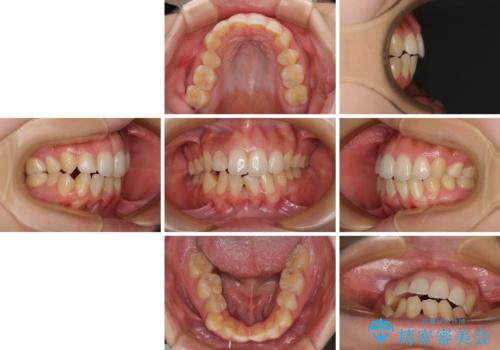

- 学生時代の抜歯矯正の後戻りが気になり、再矯正を希望して来院された患者様です。

マウスピース矯正は継続する自信がなく、気になるところを短期間で改善したいとのことで、ワイヤー装置にて矯正治療を行うこととしました。

詰め物で隠していた下顎前歯の隙間は、歯軸を改善することで詰め物を除去しても隙間が目立たなくなりました。